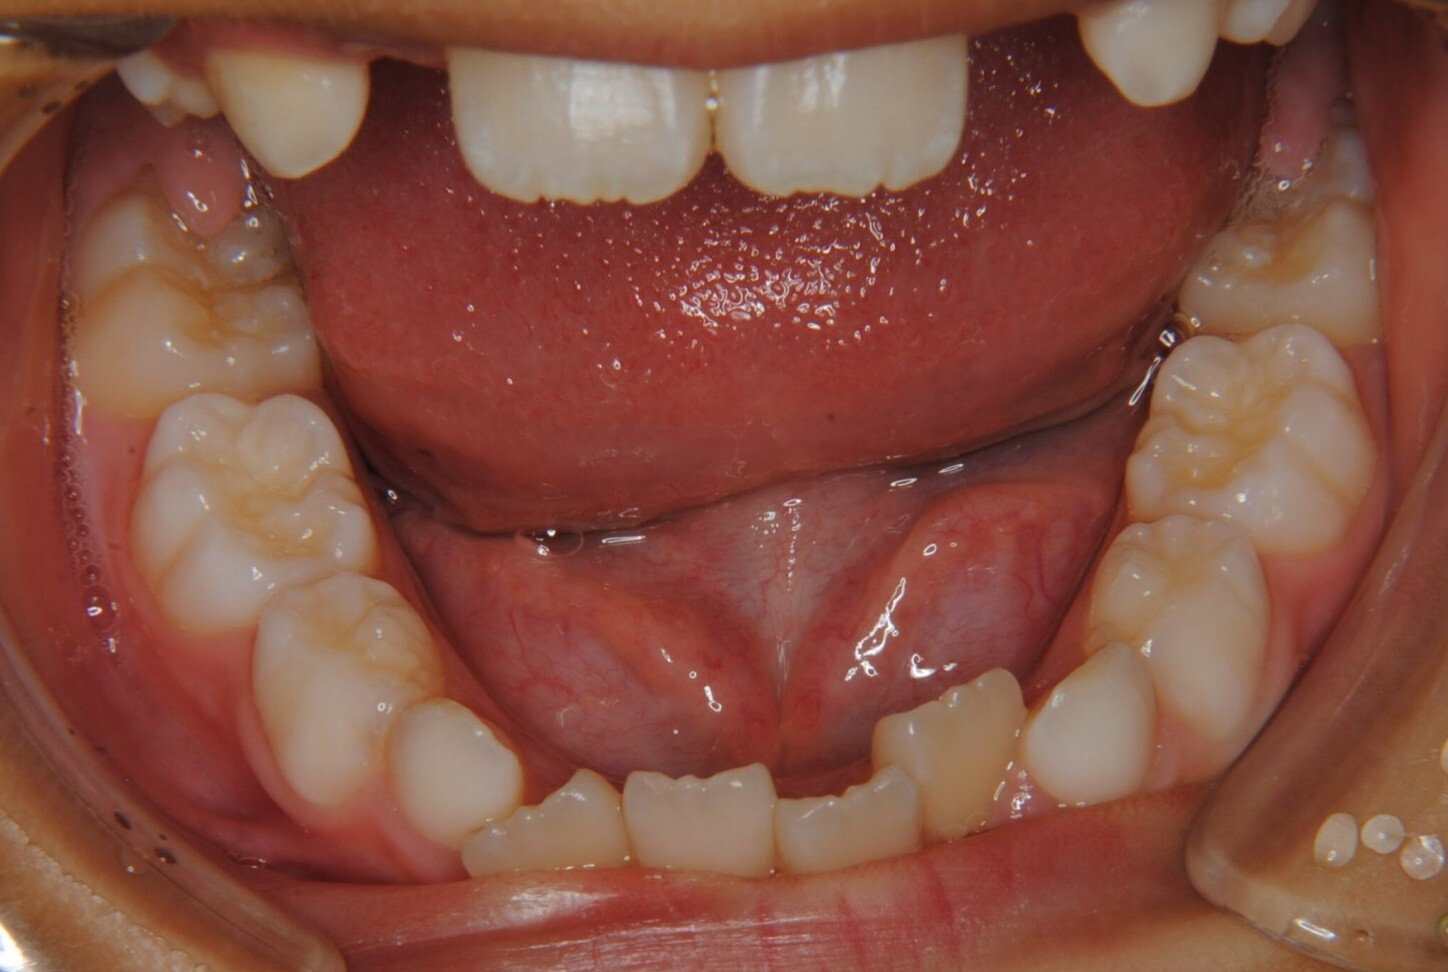

①主訴:下の前歯のデコボコ

②診断名:Ⅰ級叢生

③年齢:初診時(左写真)8歳6か月、終了時(右写真)11歳4か月

⑧リスクと副作用:特に大きなリスクや副作用はありませんでした。拡大床装着直後は違和感があったようですが、特に痛みを感じることなく6.5mmまで拡大できました。その後永久歯への生え変わりも順調で、ほぼ正常な咬み合わせになりました。この後11歳4か月まで観察し、7番目の奥歯である12歳臼歯がきちんと咬んだので終了となりました。